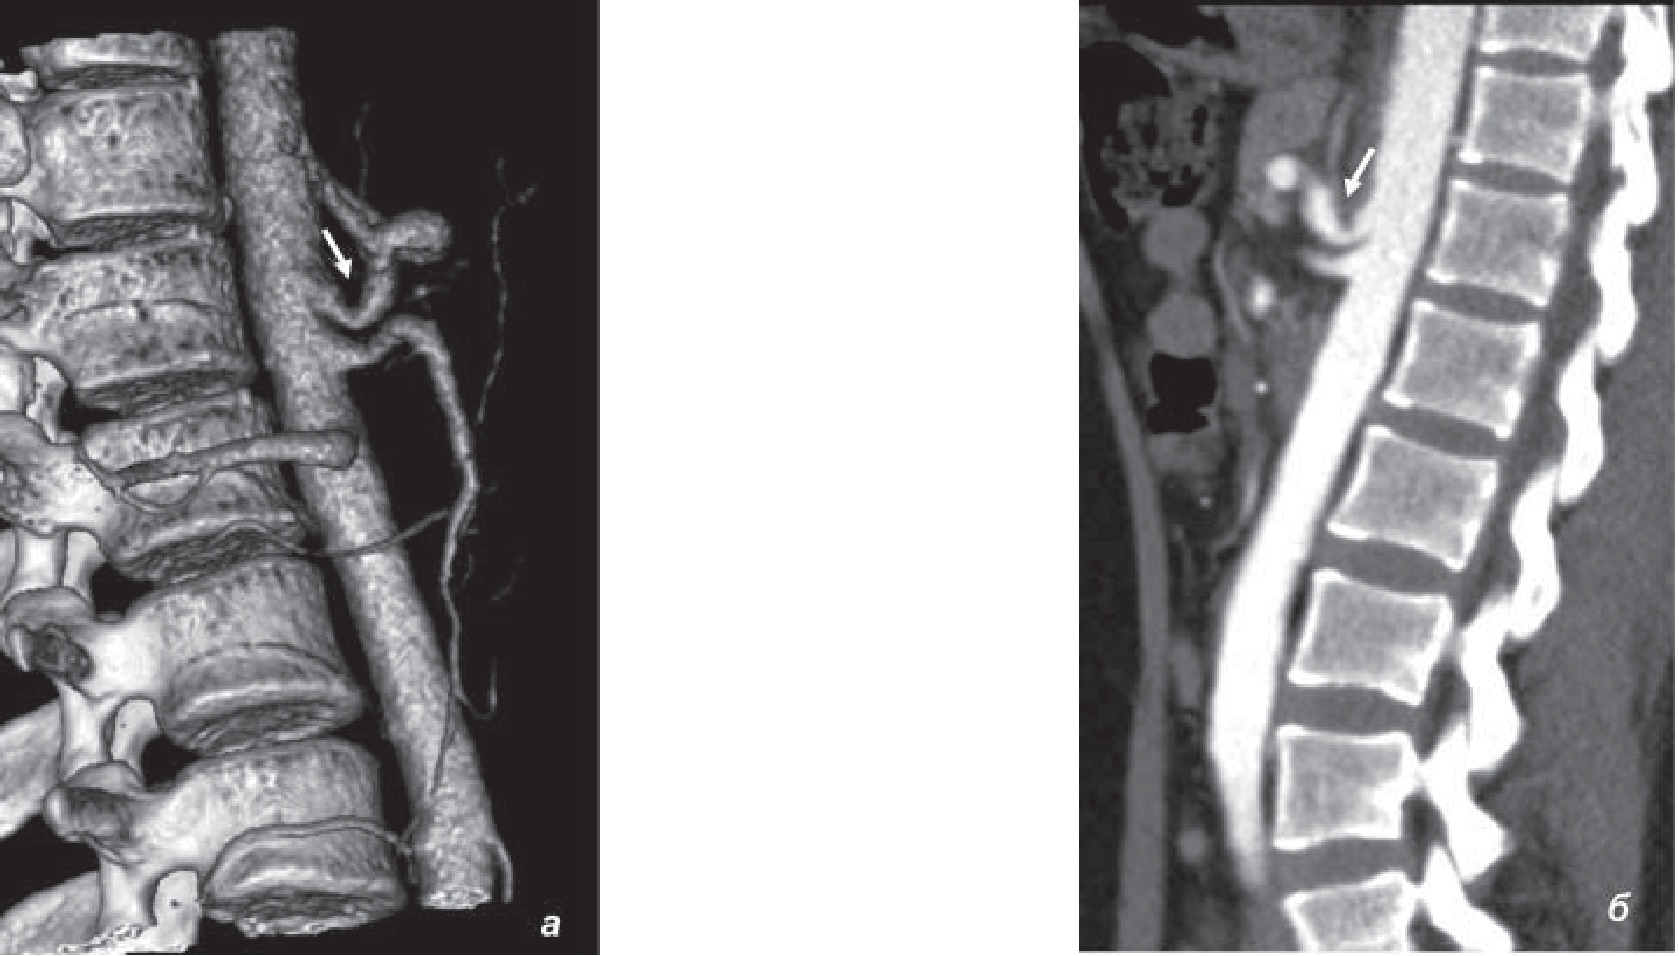

Проведенное цветное дуплексное сканирование непарных висцеральных ветвей брюшной аорты показало наличие экстравазальной компрессии ЧС (стеноз на выдохе 50–60%), что позднее подтвердила компьютерная томография (КТ) брюшной полости с контрастированием (рис. 1). На консилиуме врачей госпиталя с целью определения показаний к хирургическому лечению принято решение о проведении ангиографии висцеральных ветвей брюшной аорты. Выполненная аортография позволила определить сужение проксимальной трети ЧС около 75% (рис. 2). На повторном консилиуме было принято решение о проведении плановой хирургической декомпрессии ЧС.

Рис. 1. КТ-ангиография брюшной аорты от 08.09.2016 г. (а), КТ-картина экстравазальной компрессии чревного ствола до 60% (б)

Рис. 2. Аортография от 14.09.2016 г. Сужение просвета чревного ствола до 75%